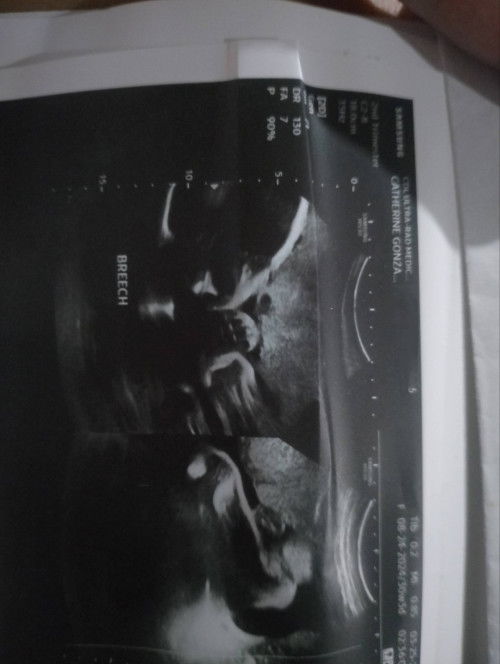

Breech baby

Mga mi 33weeks going 34 Breech si baby, iikot pakaya sya? Kung kailan malapit na saka sya umikot 😫😫